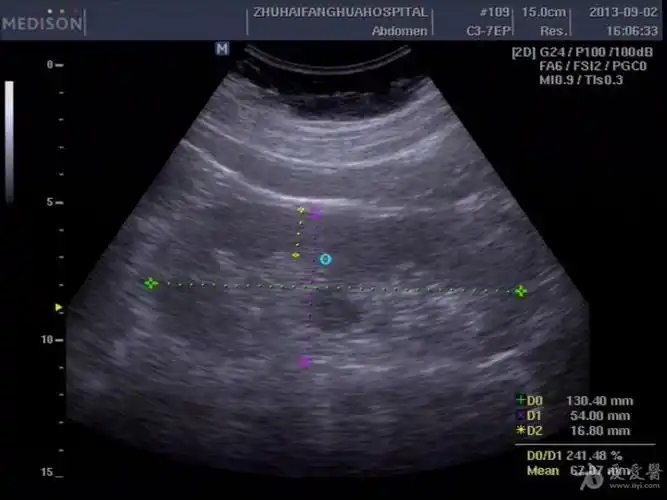

双侧双肾盂双输尿管畸形